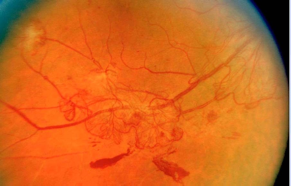

视网膜前出血与玻璃体积血

视网膜前出血

视网膜前出血(PRH)位于视网膜前部,可有液平面或呈近似圆形、连续或线性片状出血。

脱离的视网膜表面的出血也被认为是视网膜前出血。

玻璃体积血

位于玻璃体腔内的出血(比视网膜前出血位置更靠前)被称为玻璃体积血(VH)。

当存在晶状体混浊或对焦不良时,阅片医生可能难以对玻璃体出血的情况进行准确判断。

纤维增生

纤维增生(伴随或不伴随新生血管)可能会出现在视盘表面、视网膜表面或在视盘或视网膜前的玻璃体腔内。

完全萎缩的新生血管(无可见红色血流)也可被认为是纤维增生。

视网膜脱离是一种常见的糖尿病视网膜病变晚期严重并发症,可对患者造成显著的视力损伤。

糖尿病视网膜病变引起的视网膜脱离总是伴随“纤维-血管组织”的牵引。

▲ 视网膜脱离

▲ 视网膜前出血(PRH)可见于视网膜脱离的表面。